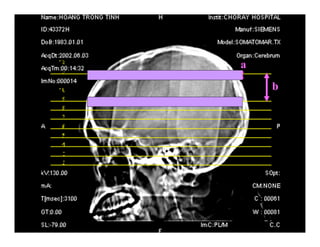

Hoï-teân Beänh vieän

Nam-Nöõ Ngaøy chuïp

Soá ID

ROI

kV, mAs

S# W/L

Hình định vị

Hình CT

Khung hình

PHIM CT

Các thông số

a

b

Độ dày lát cắt

Khoảng cách lát cắt